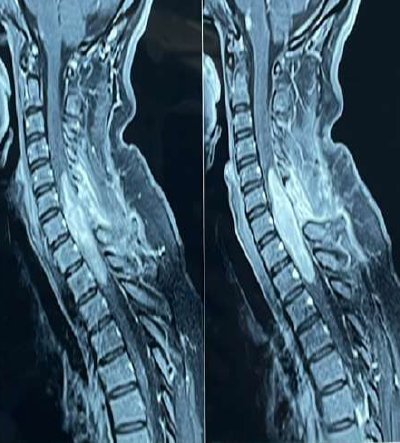

Neurosurgical treatment of unstable cervical spine due to rheumatoid arthritis: case series

JORGE ZUMAETA S, ELAR CARI C, ALFONSO BASURCO C, CESAR POLO D, JESUS CABREJOS B, PABLO PINO L, JUAN SALAS G, EDUARDO LAOS P, ROBERT BURGOS C.